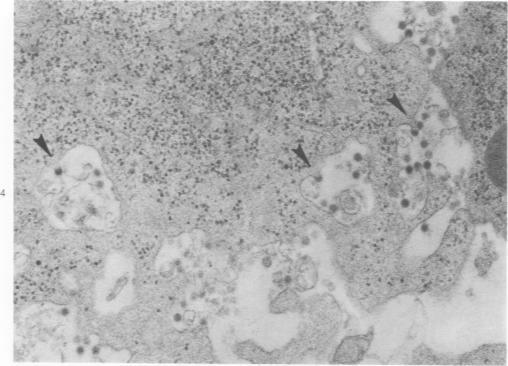

Ultrastructural, histopathologic, and virologic studies of adult hamsters infected with virulent Venezuelan equine encelphalomyelitis (VEE) virus (Subtype I-B) demonstrated precise chronologic and topographic progression of lesions and viral replication in extraneural sites. Thymus contained the earliest lesions and the highest initial and subsequent viral titers. No particular cytotropism was observed as highly efficient viral replication and severe cytonecrosis proceded. Early cortical necrosis of splenic periarteriolar lymphocytic sheath was followed by lymphoblastoid repopulation of the peripheral zone. Massive bone marrow necrosis was accompained by ultrastructural evidence of VEE viral particle production in reticulum cells, rubricytes, myeloid cells, lymphoblastoid cells, and megakaryocytes. Speed, efficiency, destructiveness, and relative sensitivity of virtually all lymphoreticular and hematopoetic cells were hallmarks of virulent VEE infection in the hamster.

对感染强毒委内瑞拉马脑炎(VEE)病毒(I - B亚型)的成年仓鼠进行的超微结构、组织病理学和病毒学研究表明,病变和病毒在外神经部位的复制呈现出精确的时间顺序和拓扑进展。胸腺出现最早的病变,且初始和后续病毒滴度最高。在高效病毒复制和严重细胞坏死过程中,未观察到特定的细胞嗜性。脾脏动脉周围淋巴细胞鞘的早期皮质坏死之后,外周区出现淋巴母细胞样细胞重新填充。大量骨髓坏死伴随着网状细胞、红细胞、髓细胞、淋巴母细胞样细胞和巨核细胞中VEE病毒颗粒产生的超微结构证据。几乎所有淋巴网状和造血细胞的快速性、高效性、破坏性和相对敏感性是仓鼠感染强毒VEE的特征。